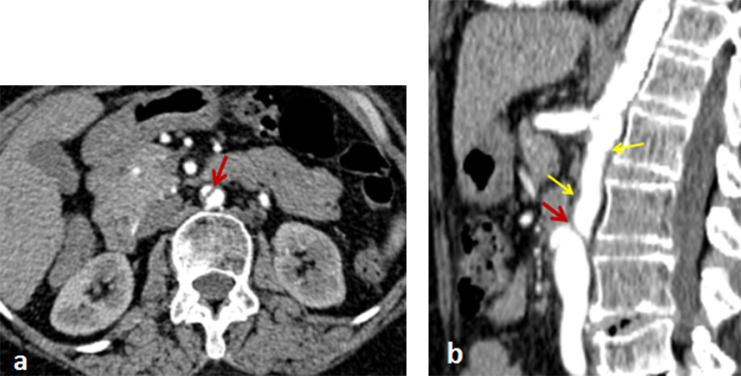

In the arterial phase, we found an incidental intimal flap on the subrenal aorta without endoluminal thrombosis (Fig. 2), denoting aortic dissection. This lesion was associated with a low attenuated, circumferential, and regular thickening of the aortic wall, compatible with Takayasu disease (Figs. 1 and 2). In the delayed phase, there was no parietal enhancement, proving the chronicity of the abnormalities. There were no atheroma plaques and no parietal calcifications.

Fig. 2.

Axial (a) and sagittal (b) sections of the abdominal CT angiography in the arterial phase, denoting intimal flap of the subrenal aorta without thrombosis (red arrow); associated with hypodense and regular parietal thickening (yellow arrows) related to Takayasu disease. (Color version available online.)

Our patient presents a nonaneurysmal and asymptomatic dissection Stanford type B of the subrenal aorta sparing the iliac arteries (Fig. 2). Dissection Stanford type B is more frequent than type A in association with Takayasu disease [6]. To our knowledge, our case is the first asymptomatic aortic dissection as a complication of Takayasu disease. The presence of a circumferential and regular parietal thickening of the aorta is typically related to an inflammatory origin that is compatible with Takayasu disease, and less likely consistent with an atheromatous background, given the absence of calcifications and the young age of the patient. The literature review reports only a few cases of aortic dissection complicating Takayasu disease, and only 7 implied an isolated abdominal aorta, all of which were symptomatic [6], [7], [8], [9], [10], [11].